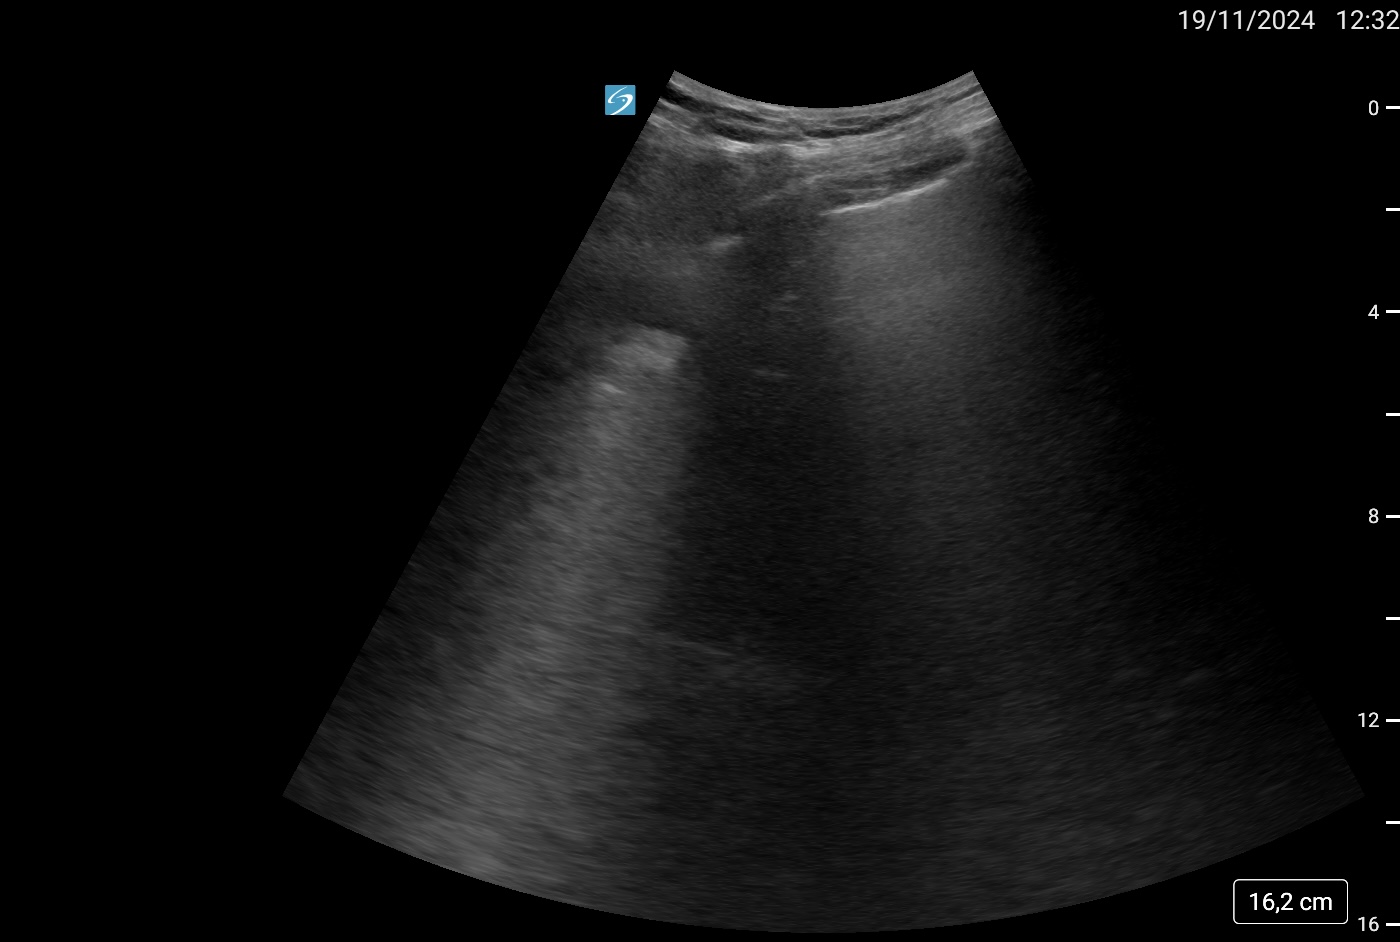

Ecografía como herramienta útil para la exploración física:

Utilidad de la ecografía como herramienta complementaria para la exploración física, aplicable tanto en el Servicio de Urgencias como en el ámbito ambulatorio.